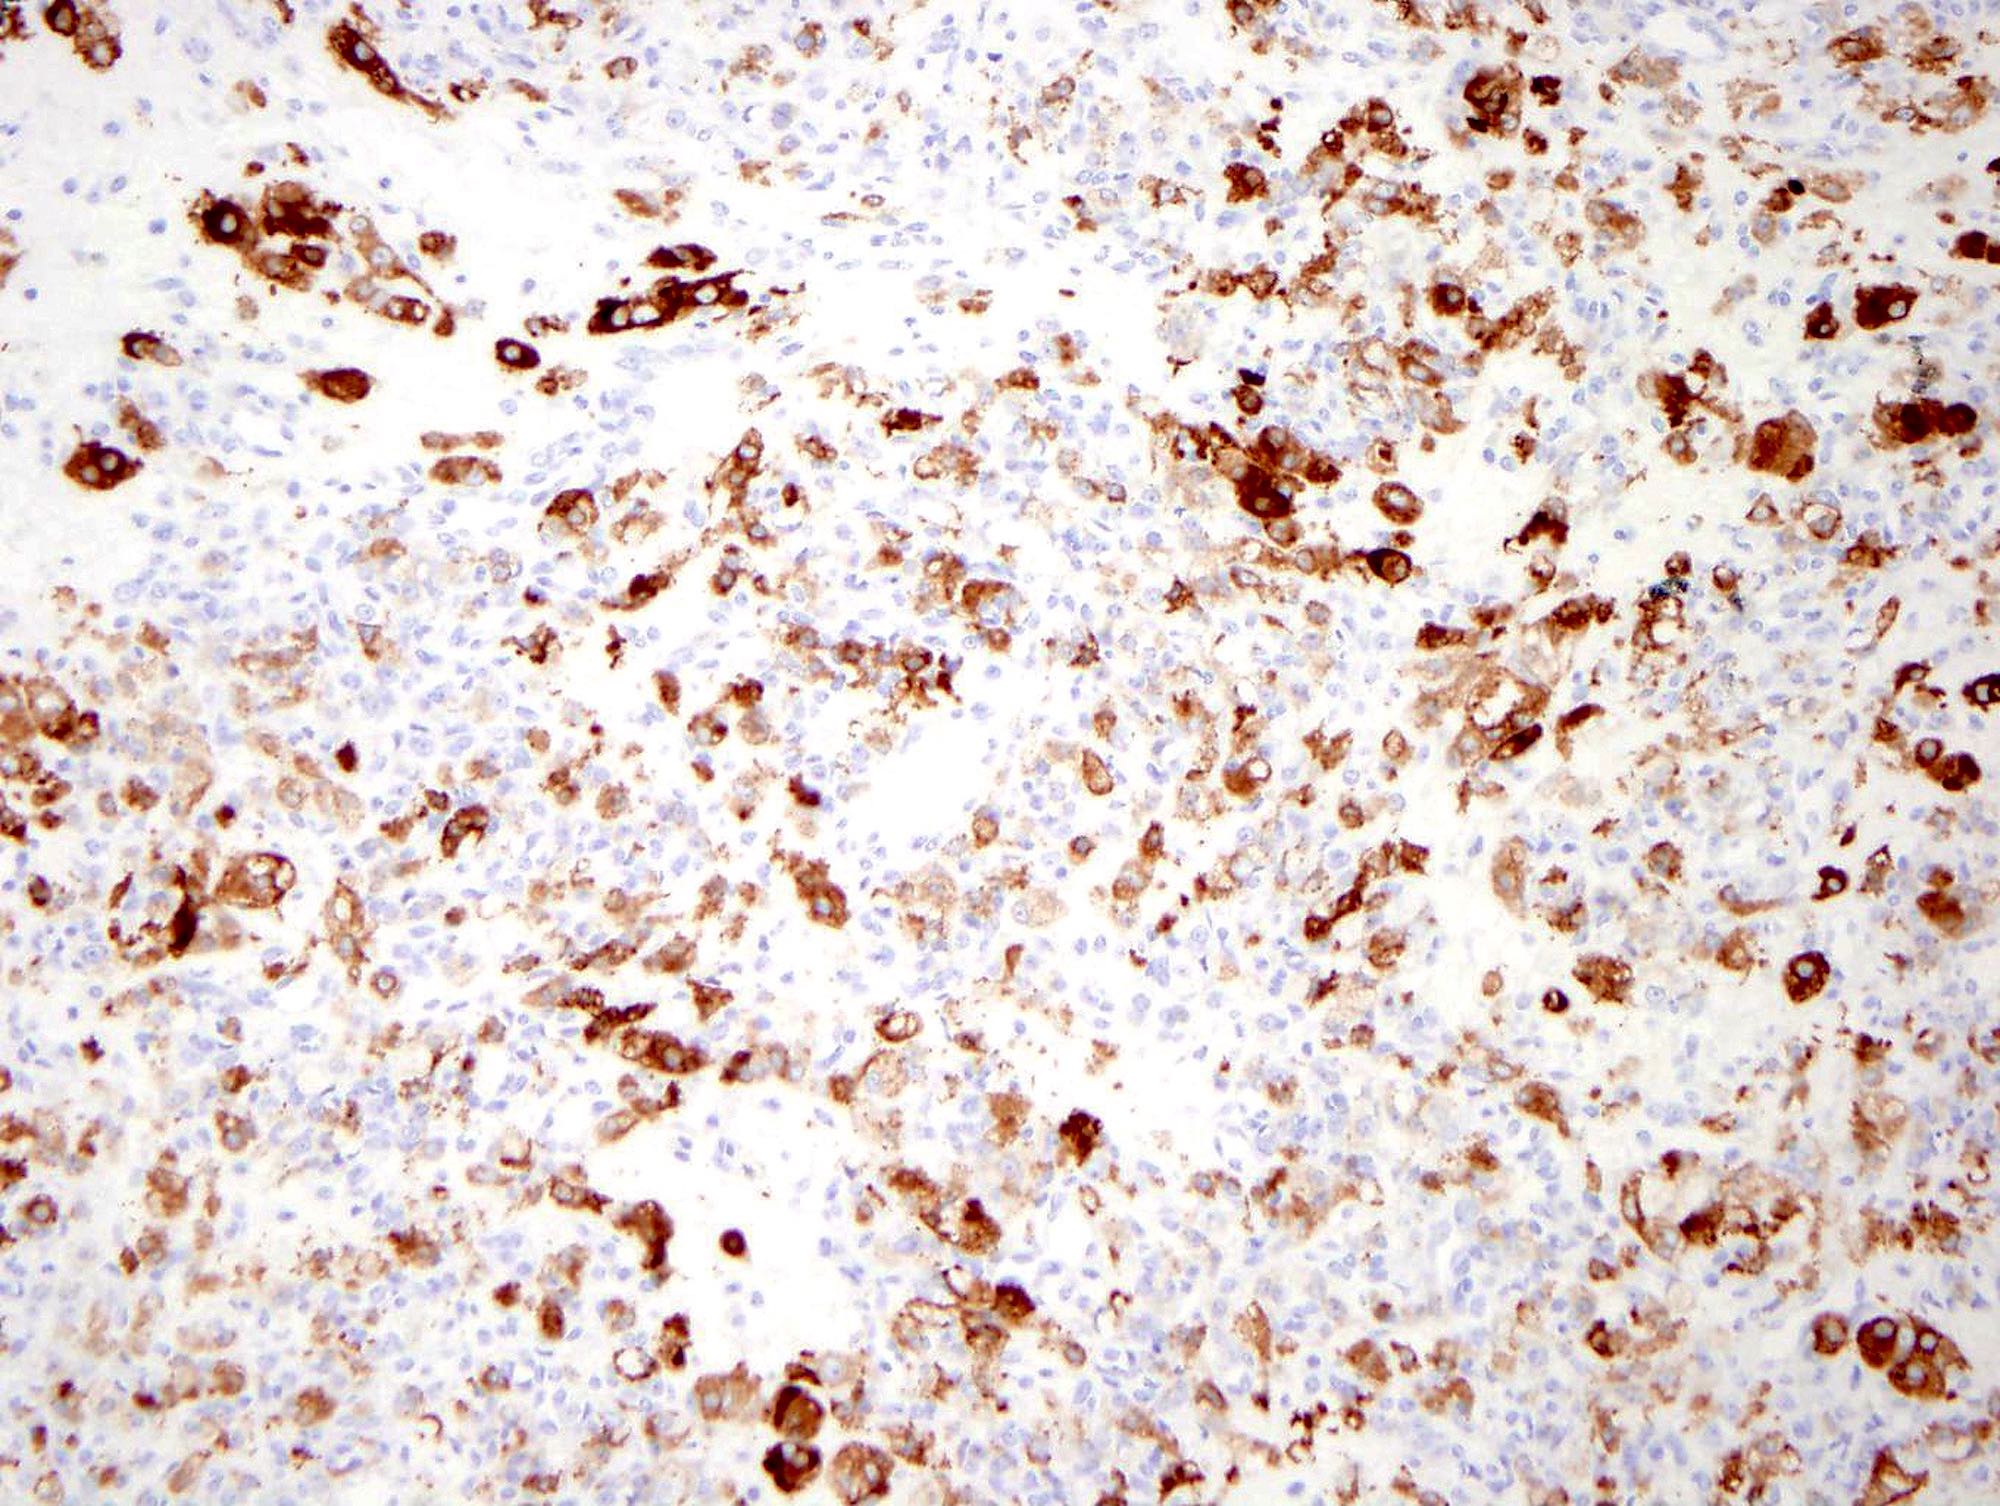

Microscopic (histologic) images

Positive stains

- Inhibin, calretinin, FOXL2

- CD10, smooth muscle actin

- Diffuse TFE3 expression in a subset of tumors (Anticancer Res 2017;37:5441)